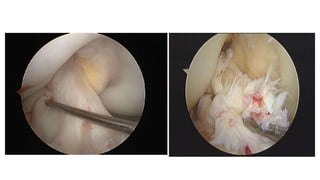

ARTHROSCOPY

• Minimally invasive (Key-hole) surgical procedure on a joint in which

an examination is done with an arthroscope.

• Arthroscopy – from Greek

• Arthro – joint

• Skopein – to look

• Arthroscope 30 degree/ 70 degree

• Fibreoptic cables